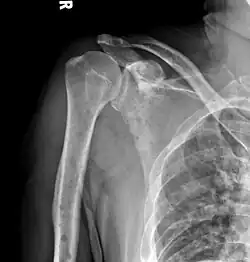

The diagnostic examination of a person with suspected multiple myeloma typically includes a skeletal survey. This is a series of X-rays of the skull, axial skeleton, and proximal long bones. Myeloma activity sometimes appears as "lytic lesions" (with local disappearance of normal bone due to resorption) or as "punched-out lesions" on the skull X-ray ("raindrop skull"). Lesions may also be sclerotic, which is seen as radiodense.[76] Overall, the radiodensity of myeloma is between −30 and 120 Hounsfield units (HU).[77] Magnetic resonance imaging is more sensitive than simple X-rays in the detection of lytic lesions. An MRI may supersede a skeletal survey, especially when vertebral disease is suspected. Occasionally, a CT scan is performed to measure the size of soft-tissue plasmacytomas. Nuclear Medicine Bone scans are typically not of any additional value in the workup of people with myeloma (no new bone formation; lytic lesions not well visualized on nuclear bone scan).

X-ray of the forearm, with lytic lesions -